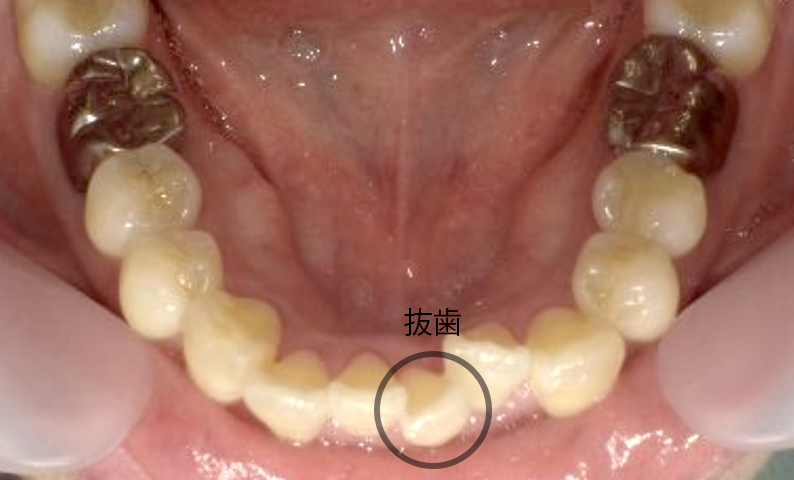

症例_002 下顎だけの部分矯正

治療期間:6ヶ月金額:21万円+税女性前歯のデコボコ下の前歯だけ